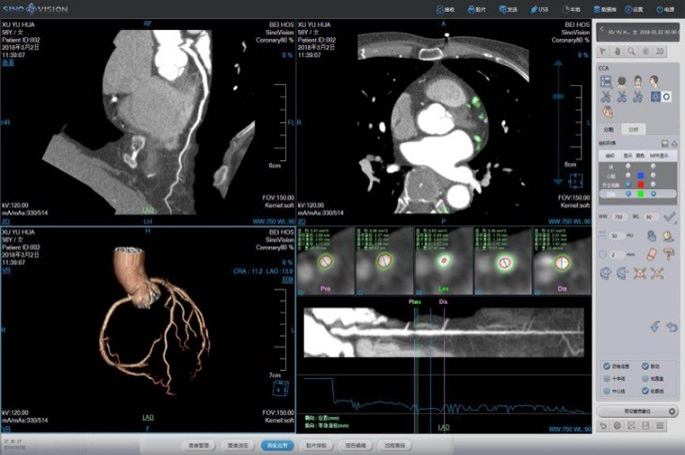

Cardiac Application Images

Coronary Calcium Scoring

Estimate the amount of calcium in the coronary arteries

• Agatston score

• Volume score

• ROI information calculation

Cardiac Viewer Images

View heart images of each phase, execute three-dimensional reconstruction and heart extracted for CT heart images, and then view patient heart by more intuitive way, diagnosis various cardiovascular diseases.

• Different phases data comparison

• 4D play

• Oblique MPR display

One Station Cardiac Diagnosis Analysis

Prospective ECG-triggered Mode Advanced Diagnosis-guided solution –ECG guided Cardiac Examination